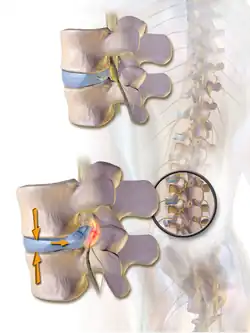

When a tear in the outer, fibrous ring of an intervertebral disc allows the soft, central portion to bulge out beyond the damaged outer rings, the disc is said to be herniated.

When the spine is straight, such as in standing or lying down, internal pressure is equalized on all parts of the discs. While sitting or bending to lift, internal pressure on a disc can move from 1.2 bar (17 psi) (lying down) to over 21 bar (300 psi) (lifting with a rounded back). Herniation of the contents of the disc into the spinal canal often occurs when the anterior side (stomach side) of the disc is compressed while sitting or bending forward, and the contents (nucleus pulposus) get pressed against the tightly stretched and thinned membrane (annulus fibrosus) on the posterior side (back side) of the disc. The combination of membrane-thinning from stretching and increased internal pressure (14 to 21 bar (200 to 300 psi)) can result in the rupture of the confining membrane. The jelly-like contents of the disc then move into the spinal canal, pressing against the spinal nerves, which may produce intense and potentially disabling pain and other symptoms.

Illustration depicting herniated disc and spinal nerve compression -